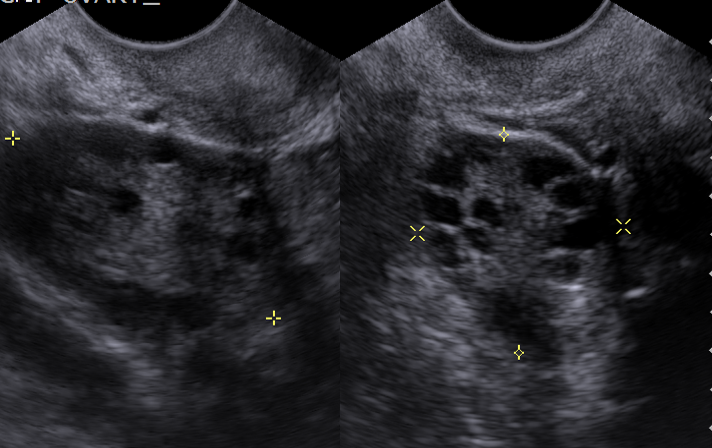

What pathological finding is shown here ?

Abnormal mass in the left adenexa - this is a transabdo scan